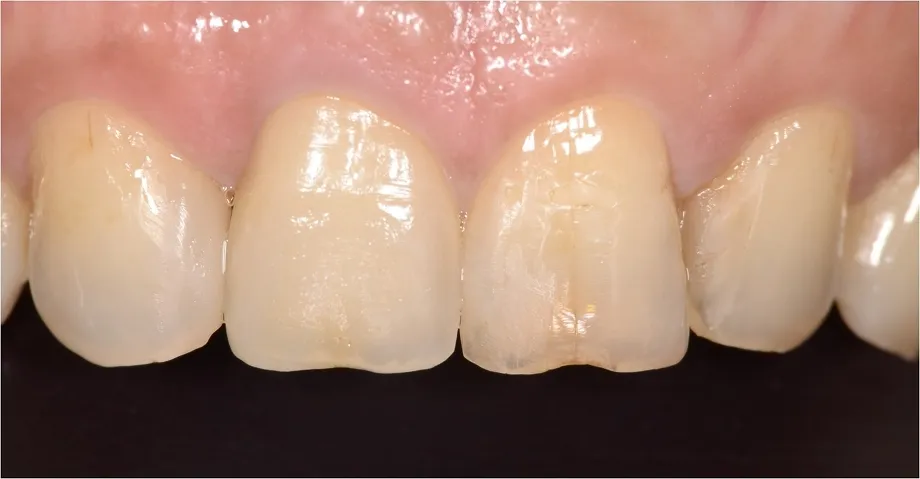

① セラミック専門の技工士による天然歯の再現・スマイルラインの形成

セラミック専門の技工士によって、天然の歯を再現するとともに、あなたに最適なスマイルラインをご提案し、実現いたします。